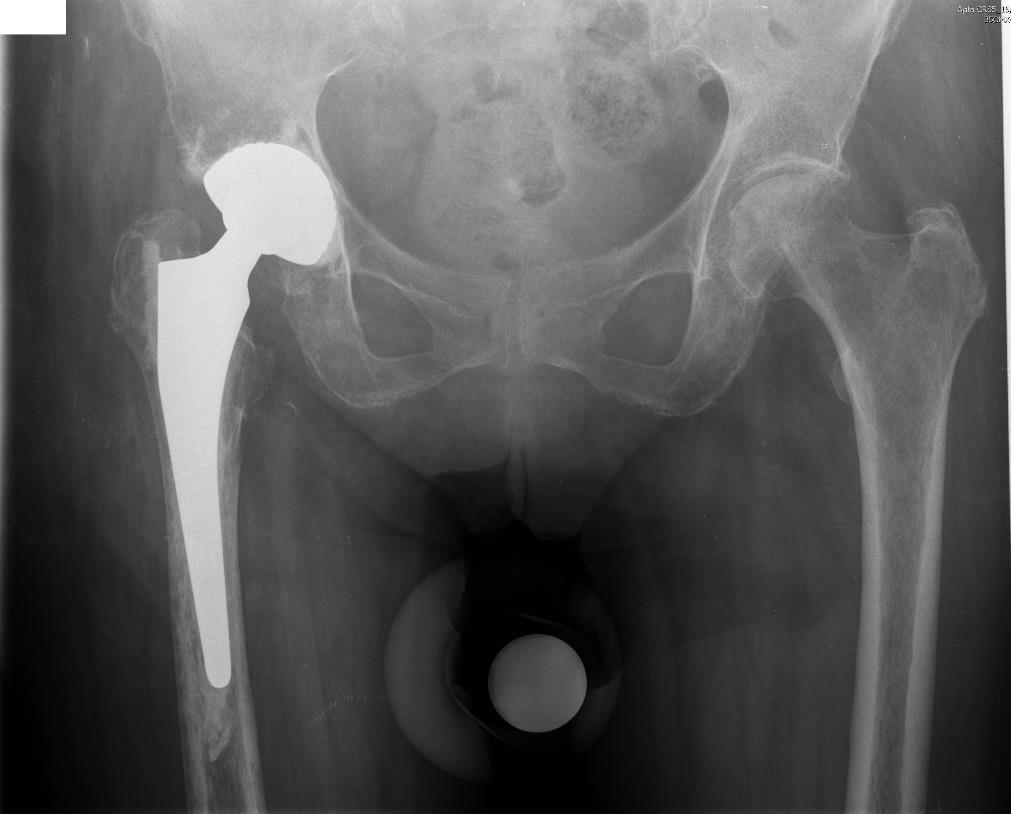

In December 2022, the patient turned to Moscow Regional Research and Clinical Institute with complaints of moderate pain in the right hip joint and loss of the supporting ability of the right lower limb, inability to move independently. The diagnosis at the initial examination was nonunion of the neck of the right femur (Figure 1), right-sided hemiparesis, osteoporosis, type 2 diabetes mellitus, hypertension, chronic gastritis.

Fig. 1. Preoperative survey radiograph of the pelvis of patient S.: nonunion of the right femoral neck, subtotal neck osteolysis, proximal displacement of the right femur by 2 cm, medial displacement of the right femur by 1 cm, severe osteoporosis.

1) Osteoporosis was assessed based on the results of dual energy X-ray densitometry: T-criterion for L1–L4 = -2.8 SD (normal range from -1 SD to +1 SD), for the left femoral neck = -2.1 SD (normal range from -1 SD to +1 SD). Determination of the cortical index of the right femur was difficult due to severity of osteoporosis corticals were visualized with difficulty (Figure 1). Diagnosis of endocrinologist: postmenopausal osteoporosis complicated with pathologic fracture of the right femur; treatment for osteoporosis was prescribed according to the clinical recommendations: sodium ibandronate monohydrate, vitamin D3, ossein-hydroxyapatite compound [6]. Regarding osteoporosis, orthopedists prescribed therapeutic exercise (TE), mechanotherapy on an exercise bike, massage;